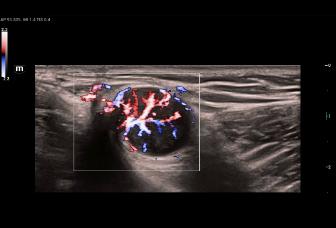

B/M/PW/HPRF/Color(ЦДК)/Color M(Цветной М-режим)/Power (Энергетический)/Directional Power Doppler Flow Imaging(Энергетический направленный допплер)

CPP Программное обеспечение для оценки индекса васкуляризации